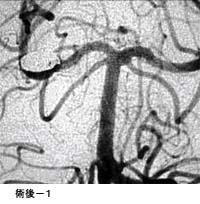

脳動静脈奇形に対する液体塞栓物質を用いた治療

治療により異常血管は閉塞されました。